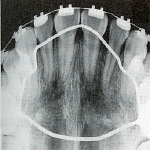

拡大前X線像

拡大前X線像 拡大直後のX線像

拡大直後のX線像 拡大後半年後のX線像

拡大後半年後のX線像

X線像

1か月で6mmほど拡大したため、急速な拡大に骨の新生が追いつかないため、拡大直後の正中縫合はまだ骨が出来ていません。そのためX線像では正中部が透過像となり黒く抜けていることが分かります。その後、約半年かけて、正中部に新しい骨が出来ると、新しい癒合部が出来ます。つまりその分だけ、上顎骨の横幅が拡大したことになります。